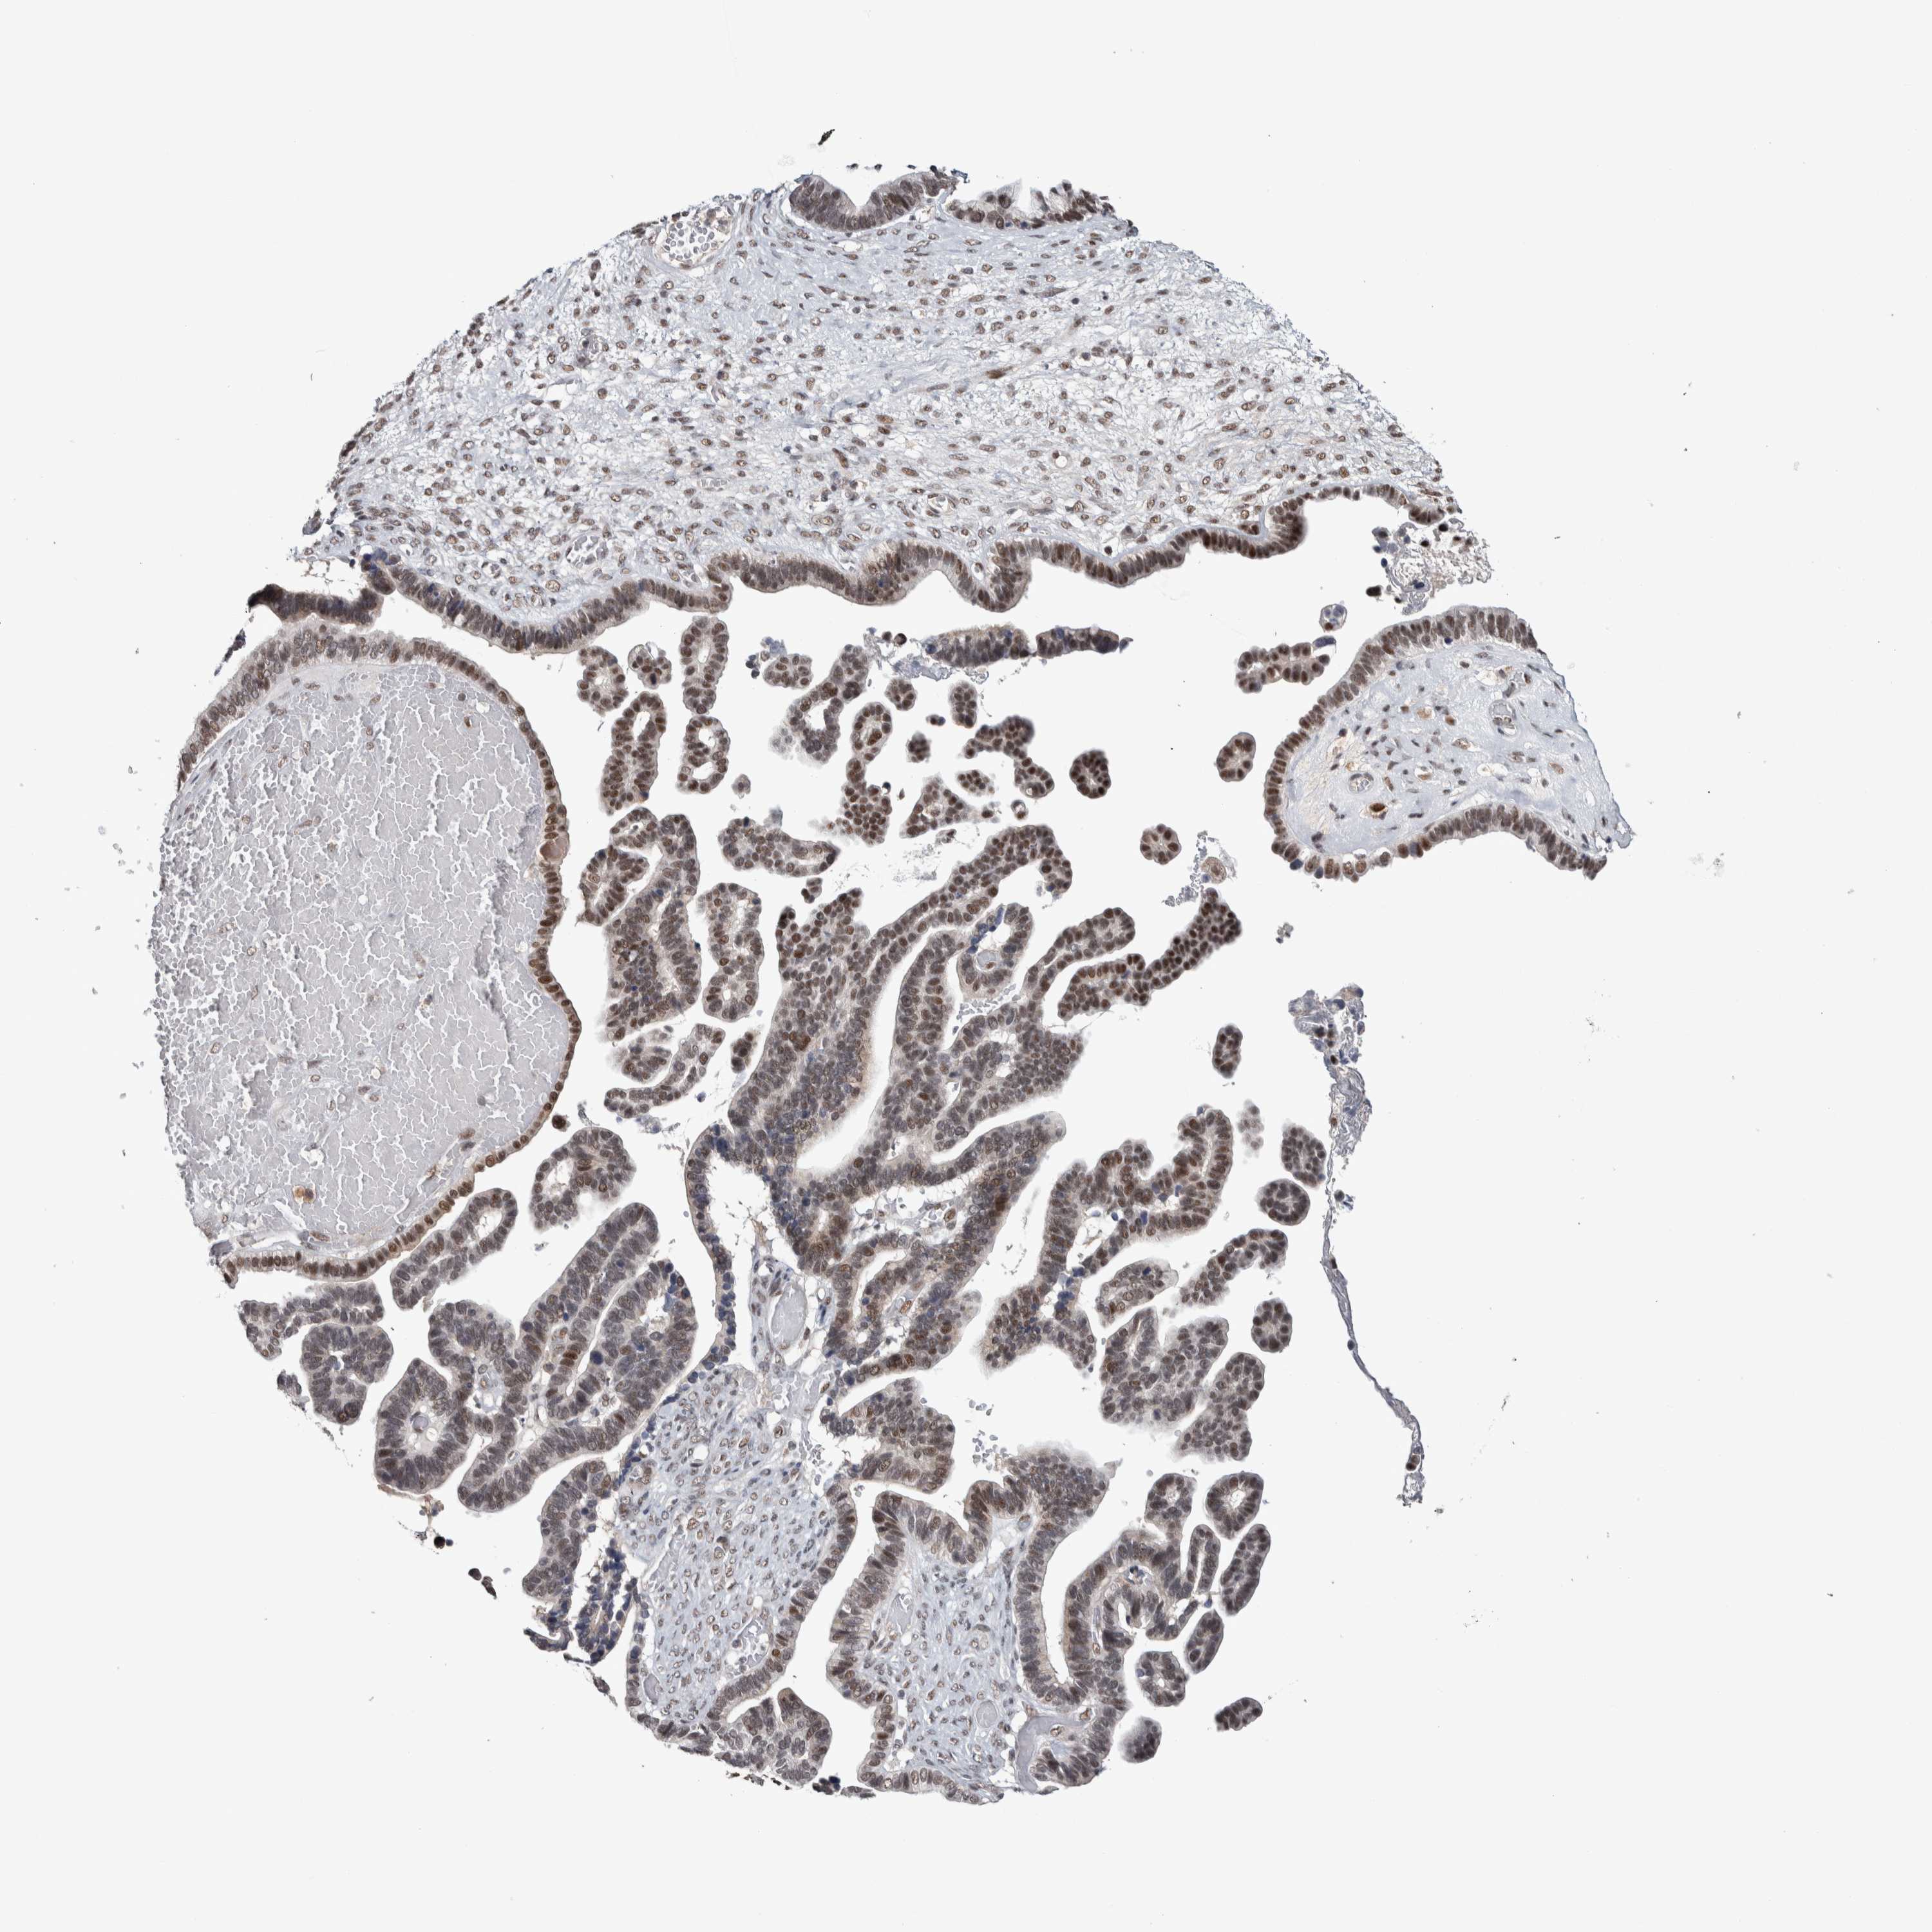

OVARIAN CANCER - Protein expressioni

A mouse-over function shows sample information and annotation data. Click on an image to view it in a full screen mode. Samples can be filtered based on level of antibody staining by selecting one or several of the following categories: high, medium, low and not detected. The assay and annotation is described here.

Note that samples used for immunohistochemistry by the Human Protein Atlas do not correspond to samples in the TCGA dataset.

Antibody stainingi

Antibody staining in the annotated cell types in the current human tissue is reported as not detected, low, medium, or high, based on conventional immunohistochemistry profiling in selected tissues. This score is based on the combination of the staining intensity and fraction of stained cells.

Each image is clickable and will lead to virtual microscopy that enables deeper exploration of all samples and also displays staining intensity scores, fraction scores and subcellular localization as well as patient and tissue information for each sample.

Antibody HPA008435

Antibody HPA024230

Staining

High

Medium

Low

Not detected

Intensity

Strong

Moderate

Weak

Negative

Quantity

>75%

75%-25%

<25%

None

Location

Nuclear

Cytoplasmic/membranous

Cytoplasmic/membranous,nuclear

Cystadenocarcinoma, serous, NOS

Carcinoma, endometroid

Cystadenocarcinoma, mucinous, NOS

Carcinoma, NOS